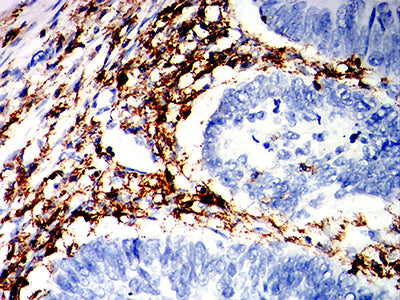

分类: 科研抗体货号: 32281别名: CIS3; SSI3; ATOD4; Cish3; SSI-3; SOCS-3应用: WB,IHC,IF,FCM反应种属: Human